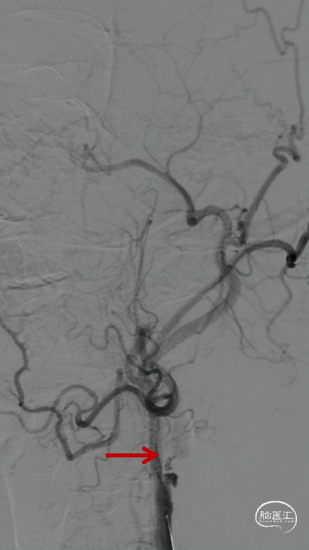

等待10分钟,复查造影颈内动脉及远端分支通畅,结束手术。DynaCT左侧外囊区域少许造影剂渗出。

术后造影

术后4h复查CT示渗出消失,左侧额叶导叶低密度灶。

术后第三天MRI示左侧额叶及导叶梗死,MRA血流通畅。患者症状明显缓解,NIHSS评分2分。